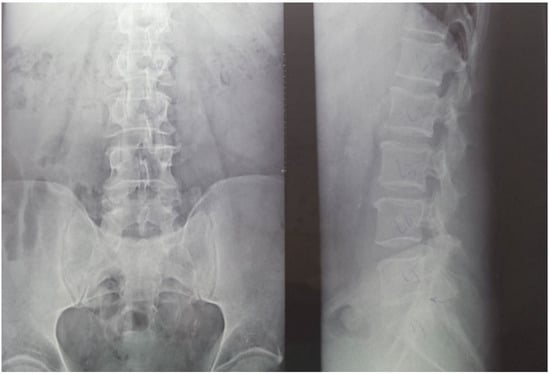

Twenty-nine non-smoking women with postmenopausal osteopenia/osteoporosis, a body mass index (BMI) of ≤25, and no physical exercise contraindications were included in the study. The subjects had not participated in any exercise program in the last 3 months, and all of them were sedentary people (less than 60 min of exercise per week). BMD was measured using DEXA analysis (Hologic Horizon, Santa Clara, CA, USA) and radiological examination (see Figure 1 and Figure 2). Skeletal BMD can be measured using DEXA, which is considered by some authors to be one of the most effective methods of diagnosing osteoporosis or osteopenia [8]. Currently, DEXA is the standard reference for diagnosing osteoporosis [9,10]. It is a precise evaluation method that involves exposing the areas to be evaluated to a small amount of X-rays and allows the areas of interest to be objectively measured. In this method, the two X-rays are absorbed differently in the bone, and the BMD is calculated in g/cm2 using simultaneous equations. Among the results offered by DEXA investigation is some information on bone mineral content (BMC) given in g, area measured in cm3, and BMD given in g/cm2 [11]. The measurement was compared with two reference values: one for young adults (30 years, which gives a T-score) and one for people of the same age as the evaluated person (which gives a Z score) [12]. DEXA has certain strengths, such as not exposing the patient to a high dose of radiation (1–6 μSv) and having a short time scan (1–2 min). Following the DEXA investigation, the software recorded the values obtained and displayed them on the screen. The T-score obtained by the subject being examined refers to her bone mass, taking as reference an individual of the same gender with peak bone mass. A classification was established depending on the score obtained: normal bone mass density (score between −1 and 0 or higher), osteopenia (between −1.1 and −2.4), and osteoporosis (a score of −2.5 or less). The Z score obtained refers to the BMD of the scanned subject compared with a subject of the same age and weight (see Figure 2).

Medical investigations (DEXA and radiographs) were conducted by a technician and the radiographs was interpreted by a specialist. The T-score provided information on whether the subject could be included in the study (the condition being that the subjects had osteopenia or osteoporosis), and the lumbar spine BMD was the quantitative information we used to make pre- and post-test comparisons. Table 1 and Table 2 and Figure 2 present information on BMD in each vertebra, but the last and the most important result is the total BMD, which is the reference result. With the help of radiography, we used visual information about the body and height of the vertebrae, the presence or absence of vertebral fractures, and the height of the intervertebral spaces. We could also observe if the subject had a history of other pathologies that would be a contraindication to performing the training protocol. Different from the DEXA investigation, which was made at the beginning and at the end of the study, the X-ray was used only at the beginning of the study to rule out the possibility of other pathologies in the lumbar area that could prevent the subjects from participating in the program.

Figure 1. Radiological image of the subjects included in the study (X-ray of the lumbar spine). (Left side) an image in the frontal plane; (right side) an image in the sagittal plane (profile). Using radiography as an auxiliary method provides information on the height of the vertebrae, the intervertebral spaces, and on other possible associated problems that could be contraindications for participating in the training protocol.